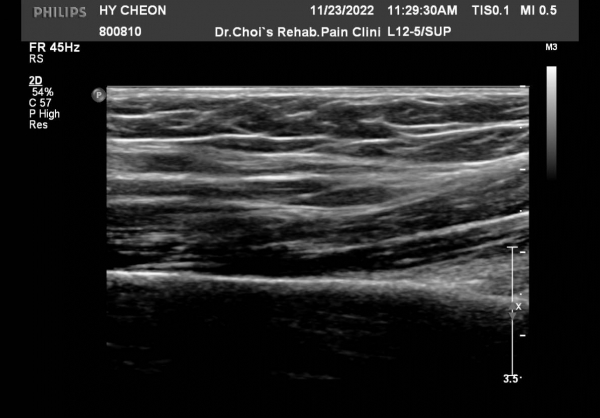

ŽÃËÀÚ¸¦ »ó¹ÚºÎ ¸»´ÜÀ¸·Î  ¿Å°Ü ÆÈ²ÞÄ¡ ºÎÅÍ ±ÙÀ§ºÎ·Î À̵¿ Çϸ鼭 Á¤Á߽Űæ Ⱦ´Ü¸é°Ë»ç¸¦

½ÃÇàÇÏ¿´´Ù(»çÁø 2).  ÆÈ²ÞÄ¡ ÁÖ¸§  ¾à  3cm ±ÙÀ§ºÎ¿¡¼­ Á¤Á߽ŰæÀÇ ÀϺΠ´Ù¹ß(fascicle)ÀÇ Àú¿¡ÄÚ ºÎÁ¾ÀÌ

°üÂûµÈ´Ù(»çÁø 3 , 4,  5,).